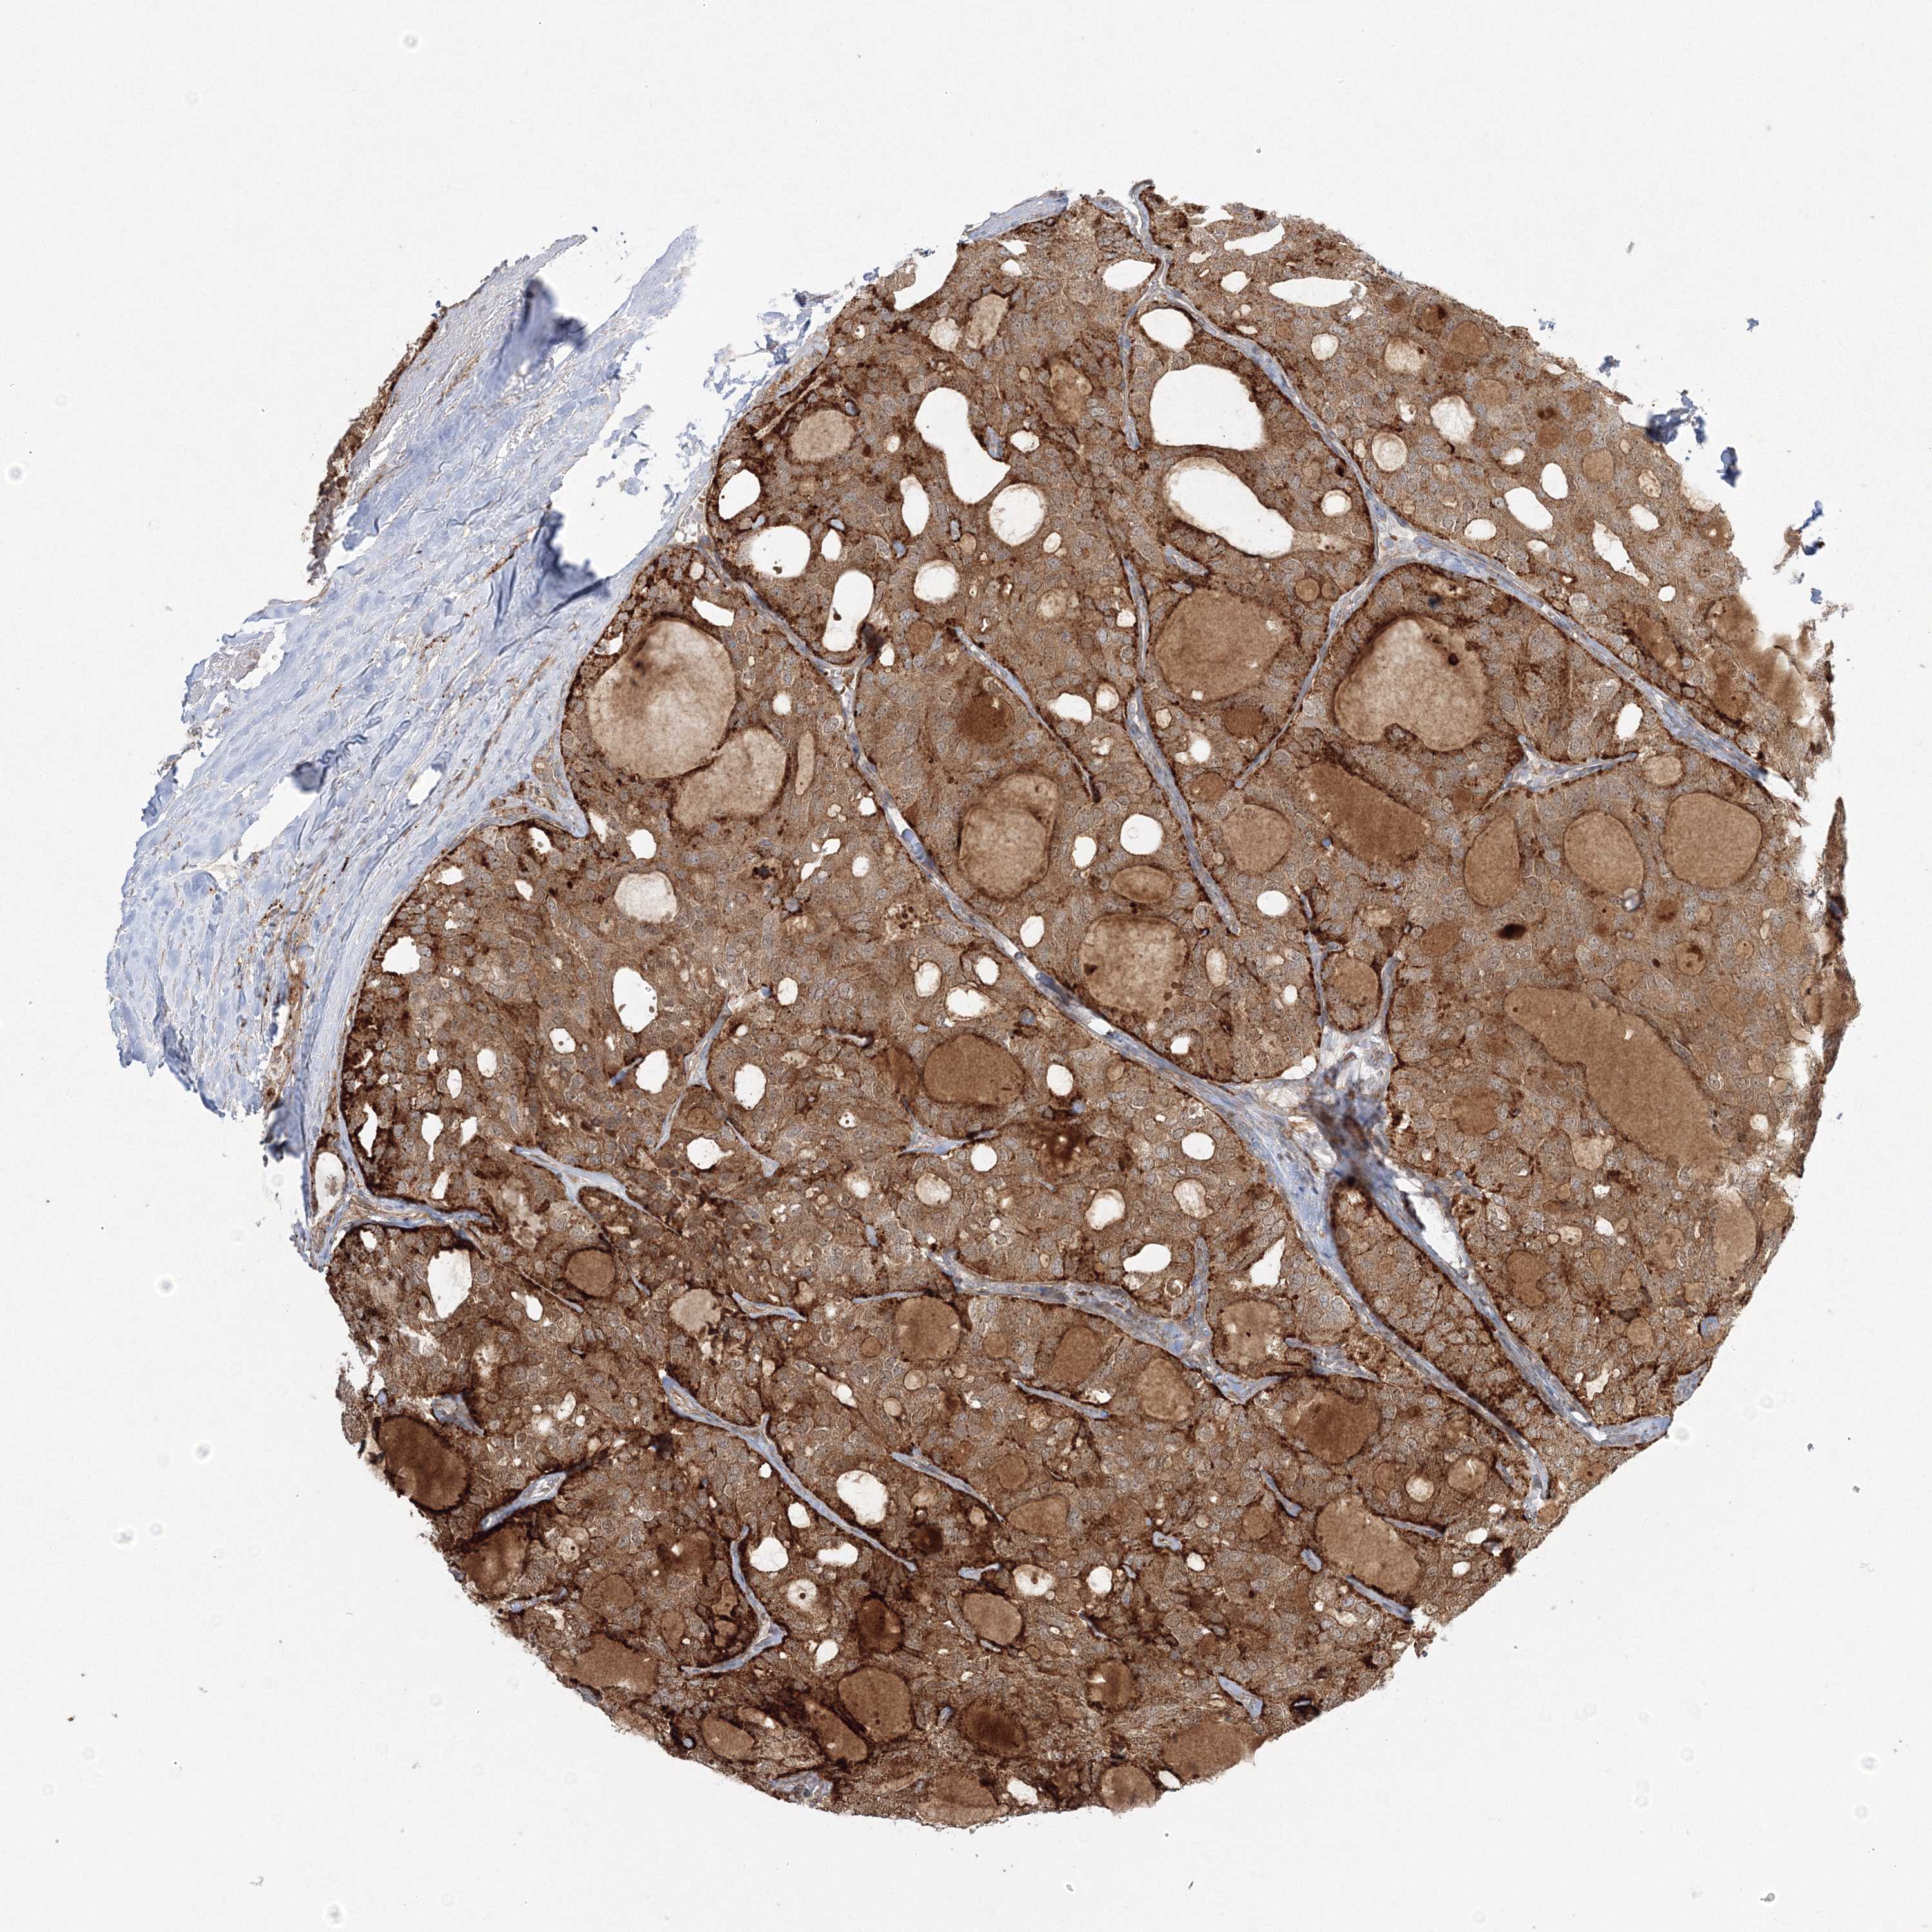

THYROID CANCER - Protein expressioni

A mouse-over function shows sample information and annotation data. Click on an image to view it in a full screen mode. Samples can be filtered based on level of antibody staining by selecting one or several of the following categories: high, medium, low and not detected. The assay and annotation is described here.

Note that samples used for immunohistochemistry by the Human Protein Atlas do not correspond to samples in the TCGA dataset.

Antibody stainingi

Antibody staining in the annotated cell types in the current human tissue is reported as not detected, low, medium, or high, based on conventional immunohistochemistry profiling in selected tissues. This score is based on the combination of the staining intensity and fraction of stained cells.

Each image is clickable and will lead to virtual microscopy that enables deeper exploration of all samples and also displays staining intensity scores, fraction scores and subcellular localization as well as patient and tissue information for each sample.

Antibody HPA036295

Antibody HPA036296

Staining

High

Medium

Low

Not detected

Intensity

Strong

Moderate

Weak

Negative

Quantity

>75%

75%-25%

<25%

None

Location

Nuclear

Cytoplasmic/membranous

Cytoplasmic/membranous,nuclear

Papillary adenocarcinoma, NOS

Follicular adenoma carcinoma, NOS